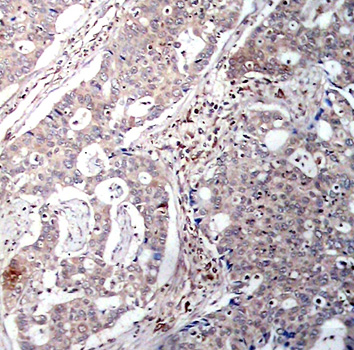

Immunohistochemical analysis of paraffin-embedded human breast carcinoma tissue using Phospho-NFKBIB-S23 antibody.

Tested applicationsIHC

Recommended DilutionIHC 1:50 - 1:100